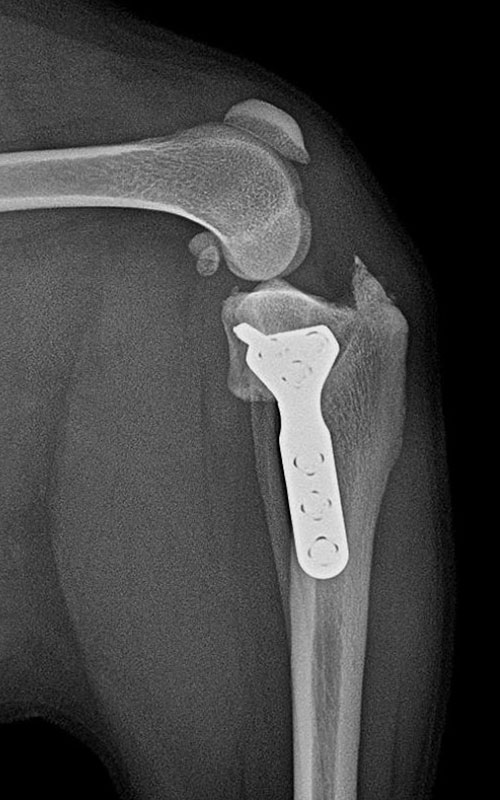

TPLO-M 2.4 with Smartvet polyaxial symmetrical TPLO plate (R15)

2.4 polyaxial butress symmetrical TPLO plate:

can be used with locking, polyaxial 2.4 torx head screws, the shift is 2.5mm. (for 5-12 kg dogs). In both cases, the insertion direction of the screws can be changed (polyaxiality !!!) to avoid the scew insertion into the joint.

The insertion errors shown in the images were due to our routine.

The modification of TPLO is intended for the simultaneous correction of MPL and RACL. The new plate provides a high degree of stability and the polyaxiality gives the surgeon a high degree of freedom in choosing the direction of the screw insertion.